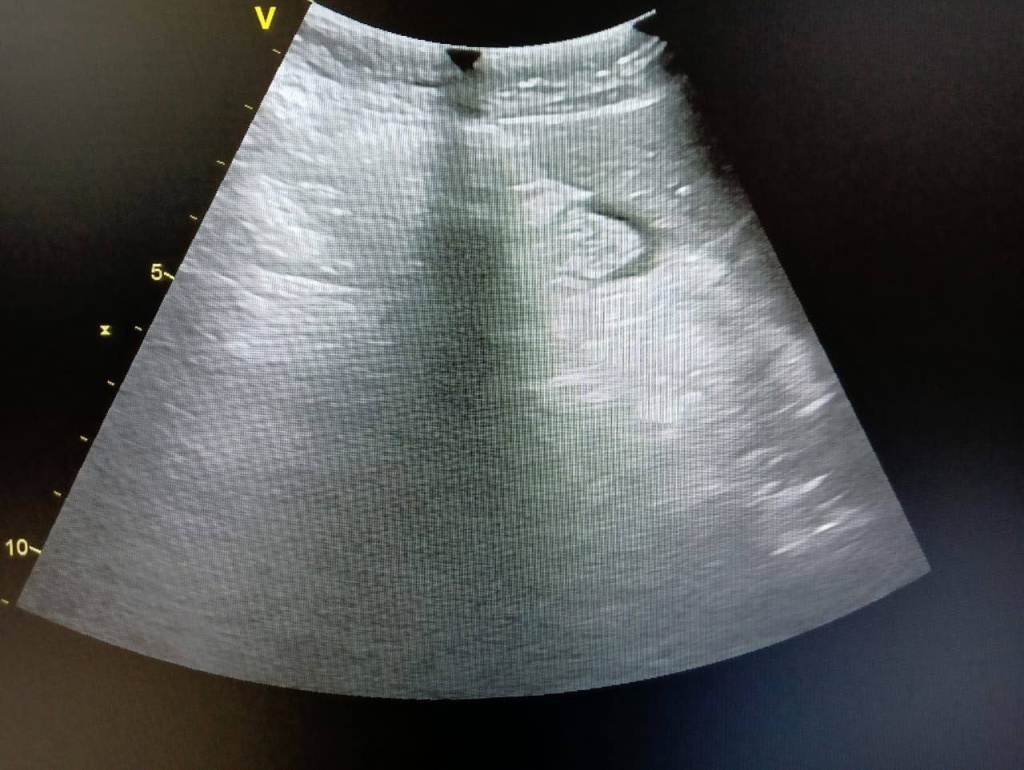

Наблюдаемая картина:

- На изображении присутствуют выраженные «провалы» сигнала

- Неравномерность усиления по глубине сканирования

- Снижение диагностической ценности изображения